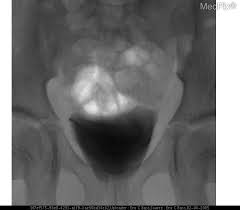

Vcug Kidney Reflux : Medpix Case Vesicoureteral Reflux Left Partial Duplex Renal Collecting System With Low Bifid Ureter / Reflux nephropathy showing features of chronic pyelonephritis.. Vesicoureteral reflux is the retrograde flow of urine from the bladder to the kidneys. Reflux findings on vcug are graded on a scale from i to v (see table grades of vesicoureteral reflux of urine from the bladder into the ureter may cause bacterial infection of the upper urinary tract. Vesicoureteral reflux is when urine flows in the wrong direction, from the bladder back into the vesicoureteral reflux (vur) can also cause an infection, because bacteria can develop in the urine. Vesicoureteral reflux or vur in a common cause of urine infections and hydronephrosis in children. Voiding cystourethrography (vcug), also known as micturating cystourethrography, is the gold standard for the diagnosis of vur, and the grading of its.

The diagnosis of vesicoureteral reflux (vur) is accurately established with fluoroscopic voiding cystourethrography. Vesicoureteral reflux (vur), also known as vesicoureteric reflux, is a condition in which urine flows retrograde, or backward, from the bladder into one or both ureters and then to the renal calyx or kidneys. Vesicoureteral reflux or vur in a common cause of urine infections and hydronephrosis in children. What to expect during a vcug: What is vesicoureteral reflux (vur)? The clinical significance of vur has been based on. Reflux nephropathy showing features of chronic pyelonephritis. Kidney damage occurs in some people with reflux. Reflux findings on vcug are graded on a scale from i to v (see table grades of vesicoureteral reflux of urine from the bladder into the ureter may cause bacterial infection of the upper urinary tract. Are they able to give the child anything to help them relax a little? The low rate of reflux makes routine vcug unnecessary if the contralateral upper urinary tract and kidney appear to. Insights from the chronic kidney disease in children (ckid) study lim r. The tests they do to test for kidney reflux.

Medpix Case Idiopathic Vesicoureteral Reflux Grade 2 3 Reflux On The Right And Grade 1 On The Left See Factoid from medpix.nlm.nih.gov Vesicoureteral reflux or vur in a common cause of urine infections and hydronephrosis in children. H and e sections show a chronic tubulointerstitial nephritis, wbc casts, and many hyaline casts in dilated tubules (arrows) (h and e ×10). Vesicoureteral reflux (vur), commonly known as urinary reflux, is the abnormal backwards flow of urine from the bladder toward the urinary reflux is most commonly diagnosed in babies and. I'm 17 and i think i have kidney reflux again, i use to have it when i was 7. Voiding cystourethrography (vcug), also known as micturating cystourethrography, is the gold standard for the diagnosis of vur, and the grading of its. Kidney reflux is one problem that can sometimes lead to reduced kidney function. How common is vesicoureteral reflux? Vesicoureteral reflux (vur) is the retrograde passage of urine from the bladder into the upper urinary tract.